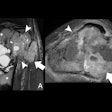

AI produces synthetic 3T MR images from portable scans